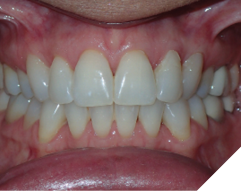

The majority of the orthodontic practices offer a period of “supervised retention” to their patients and communicates the customized retention recommendation with the patient’s general dentists. It is extremely important to work as a team to achieve long term clinical success in maintaining a functional bite and aesthetic smile. The general dentists continue to see their patients on a regular basis and have an opportunity to assess the orthodontic retainers and the bite after the supervised retention period is completed by the orthodontists. With great care, orthodontic retainers would serve for a long time (Fig. 1) without any major issues. However, in some cases, the failure to notice the clinical problems early on results in functional issues that would require a comprehensive orthodontic treatment to correct it (Fig. 2).

Fig. 1A

Fig. 1B

Fig. 1C